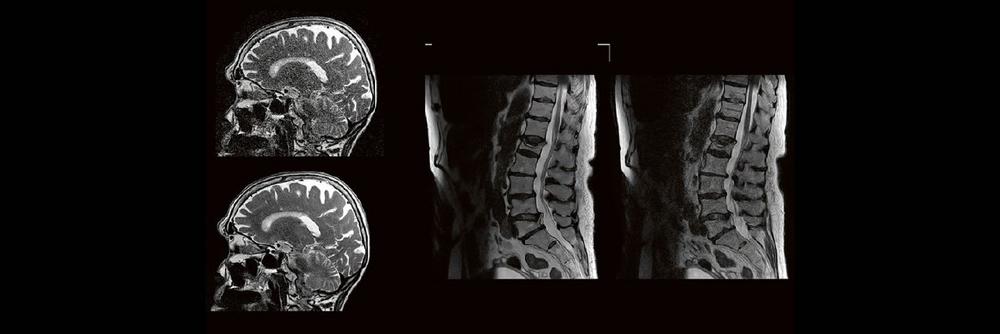

Künstliche Intelligenz spielt in der klinischen Anwendung eine immer größer werdende Rolle. Im radiologischen Sektor erfährt besonders die Magnetresonanztomographie aktuell einen regelrechten KI-Hype. Kürzere Untersuchungszeiten, eine höhere Bildqualität oder eine Kombination aus Zeit und Qualität sind theoretisch möglich, doch ist die KI in der Praxis mehr als eine Spielerei? Wie aufwendig ist es diese in den Alltag der Medizinischen Technologen und Technologinnen zu integrieren?

Die Künstliche Intelligenz (KI) revolutioniert die Radiologie und kann Ärzte dabei unterstützen, medizinische Bilder schnell und genau zu analysieren und helfen, Krankheiten frühzeitig zu diagnostizieren. Hierdurch soll die Effizienz und Genauigkeit der Diagnosen und die Qualität der Patientenversorgung verbessert werden. Anhand von Beispielen werden derzeitige Anwendungen der KI in der radiologischen Diagnostik dargestellt, Grenzen aufgezeigt und zukünftige Anwendungsgebiete beschrieben.